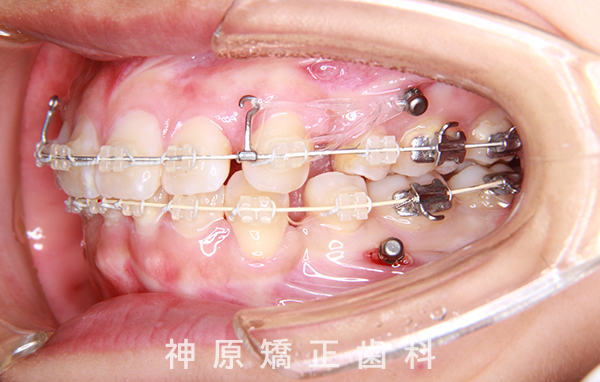

マルチブラケット装着1年後